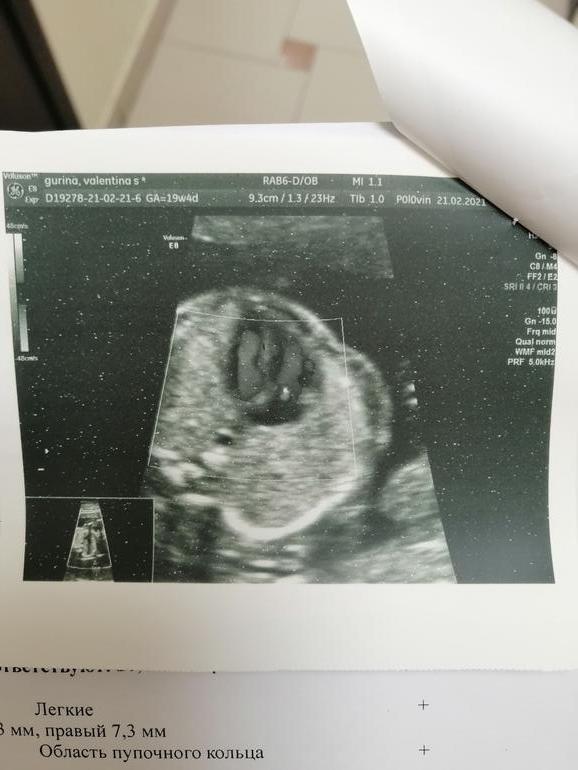

Фото дала, но мне на ней вообще ничего не понятно. На первом скрининге всё было отлично, да и сейчас всё остальное замечательно и носовая кость в норме, всё же надеюсь на ошибку врача(